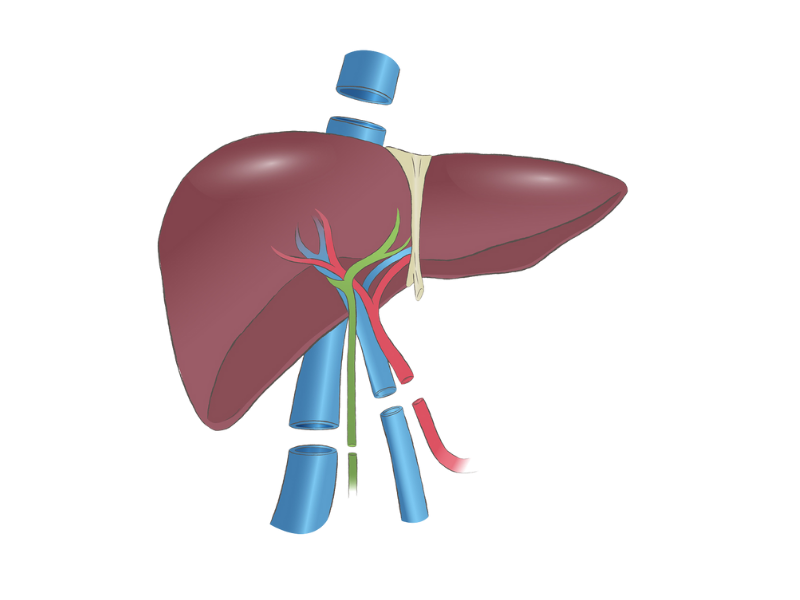

Liver transplant is a complex but life-saving procedure for patients with severe liver disease, liver failure, or certain liver cancers. It involves replacing a diseased liver with a healthy one from a living or deceased donor. At our Liver Transplant and HPB Surgery Care center, we provide comprehensive care for both adults and children, ensuring safety, precision, and excellent outcomes.